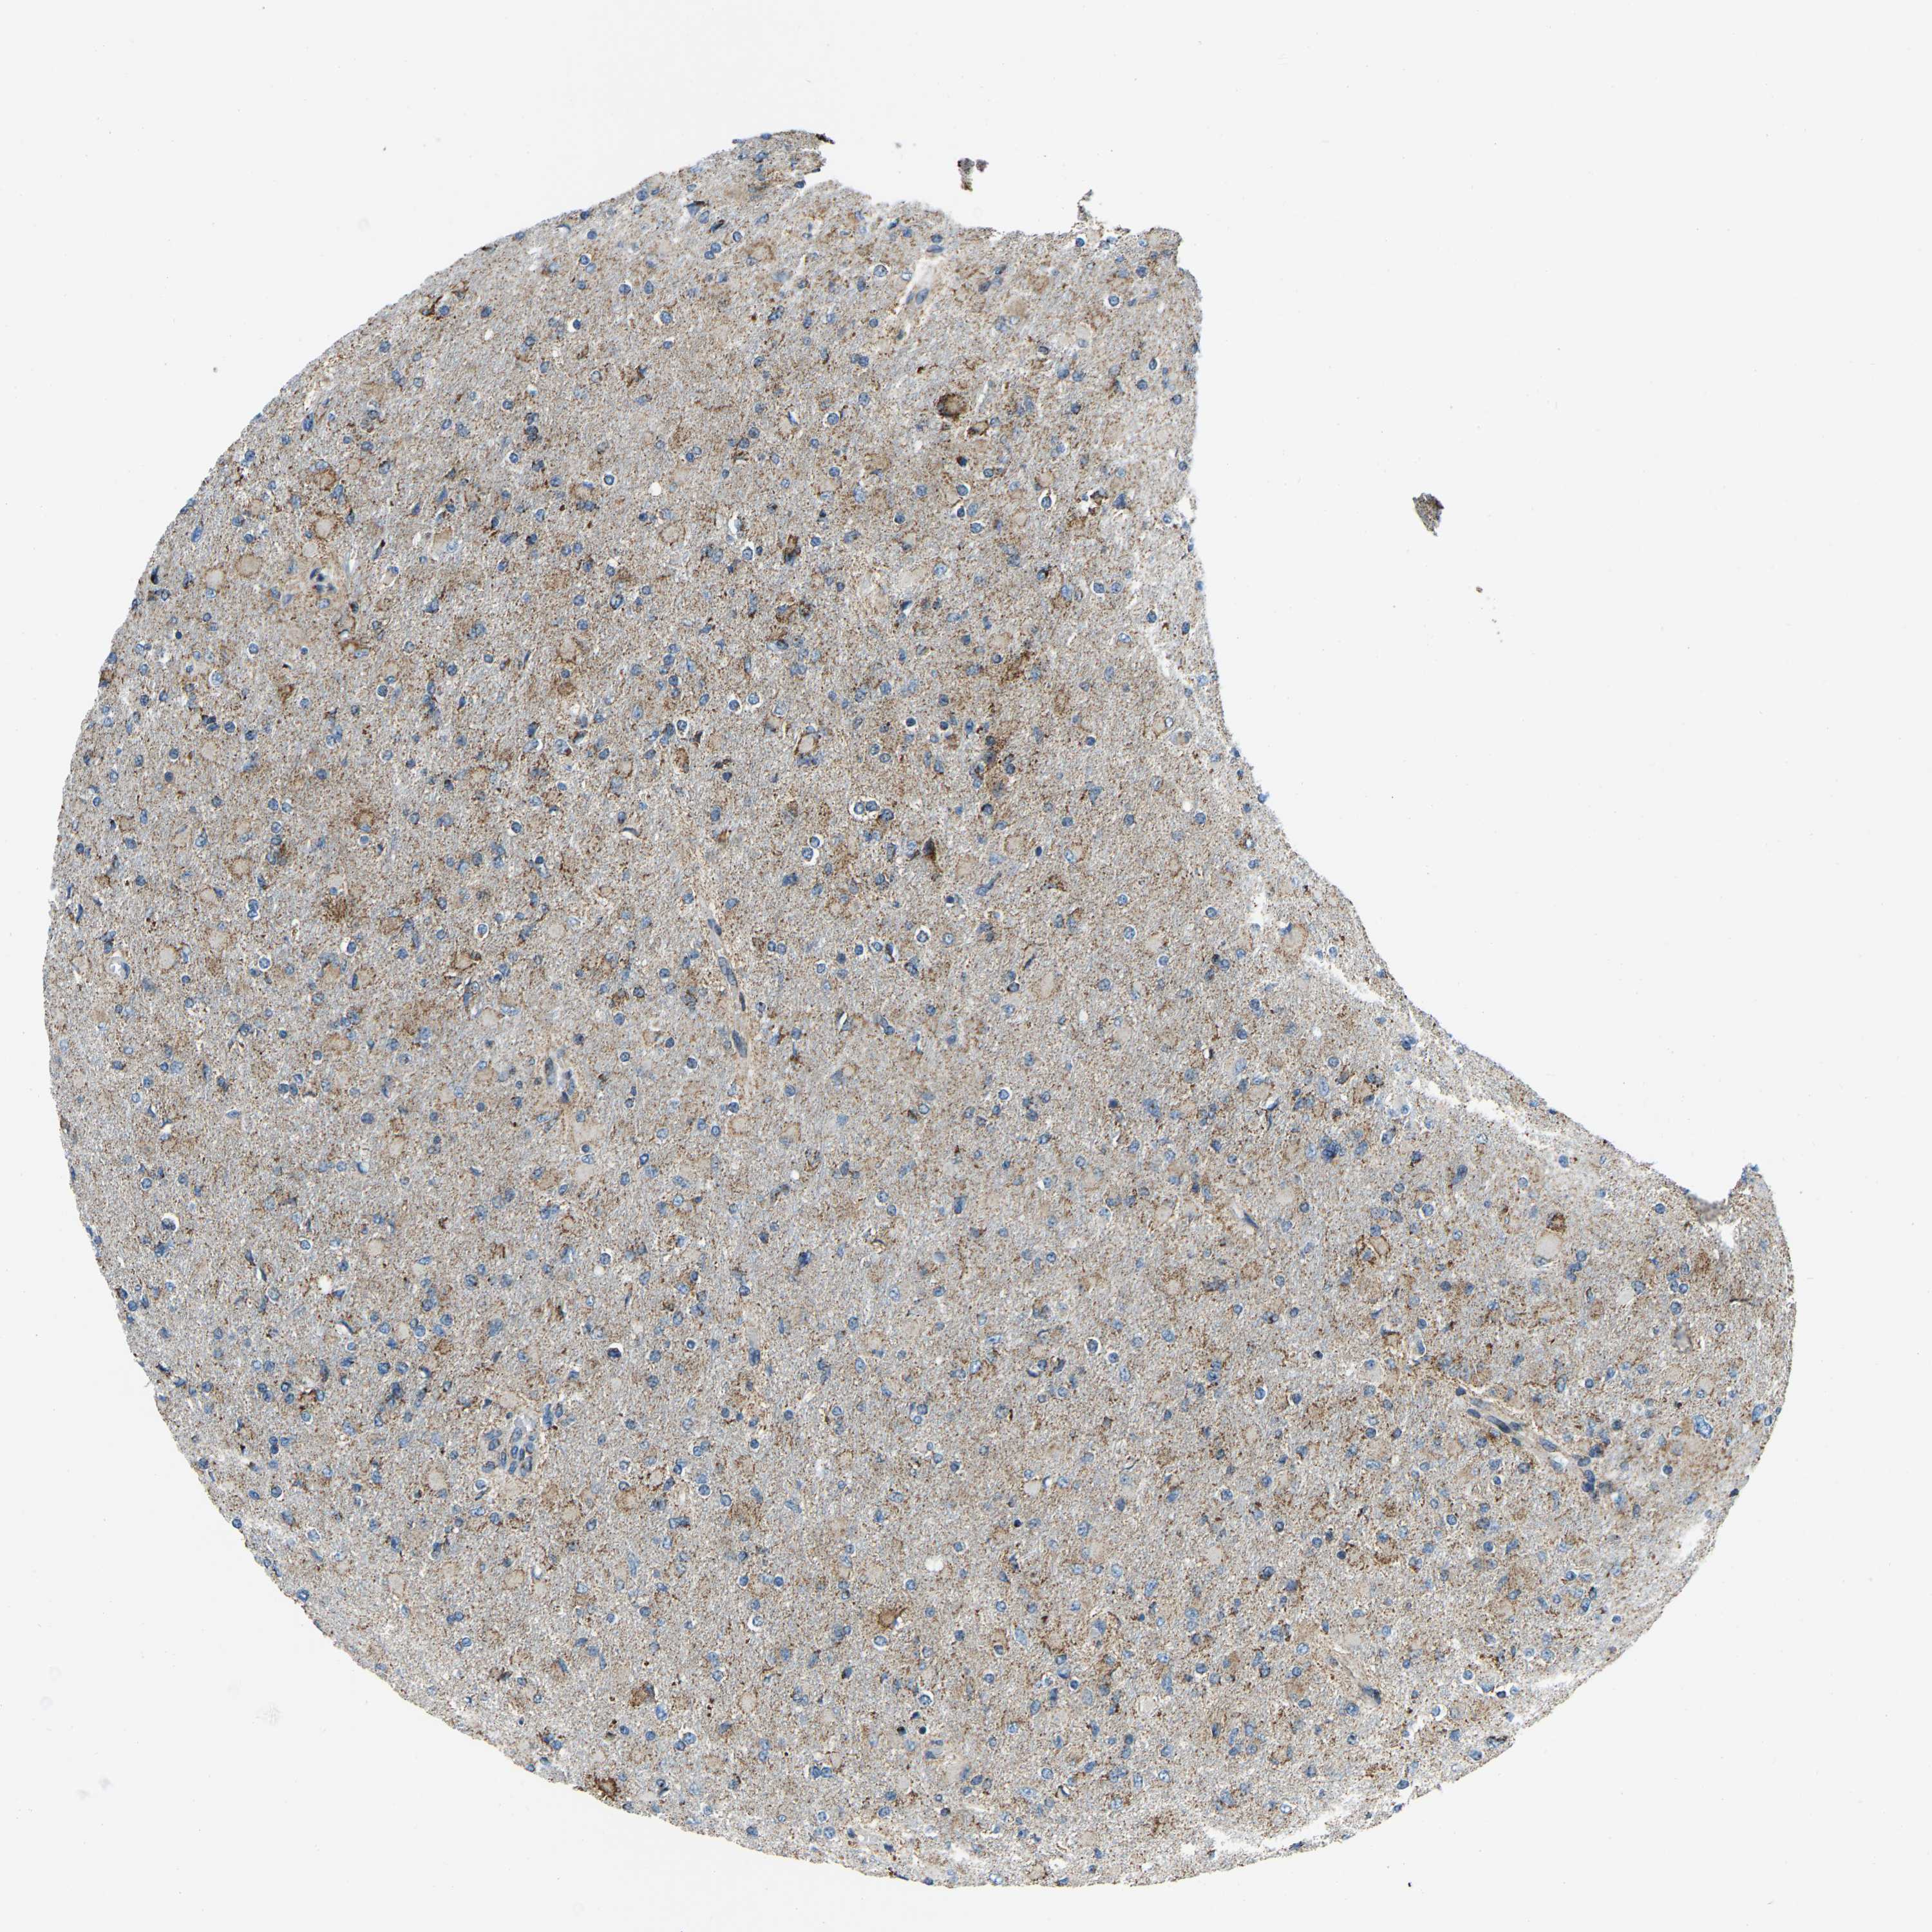

GLIOMA - Protein expressioni

A mouse-over function shows sample information and annotation data. Click on an image to view it in a full screen mode. Samples can be filtered based on level of antibody staining by selecting one or several of the following categories: high, medium, low and not detected. The assay and annotation is described here.

Note that samples used for immunohistochemistry by the Human Protein Atlas do not correspond to samples in the TCGA dataset.

Antibody stainingi

Antibody staining in the annotated cell types in the current human tissue is reported as not detected, low, medium, or high, based on conventional immunohistochemistry profiling in selected tissues. This score is based on the combination of the staining intensity and fraction of stained cells.

Each image is clickable and will lead to virtual microscopy that enables deeper exploration of all samples and also displays staining intensity scores, fraction scores and subcellular localization as well as patient and tissue information for each sample.

Antibody HPA019232

Antibody HPA021497

Antibody HPA021768

Staining

High

Medium

Low

Not detected

Intensity

Strong

Moderate

Weak

Negative

Quantity

>75%

75%-25%

<25%

None

Location

Nuclear

Cytoplasmic/membranous

Cytoplasmic/membranous,nuclear

Glioma, malignant, High grade

Glioma, malignant, Low grade